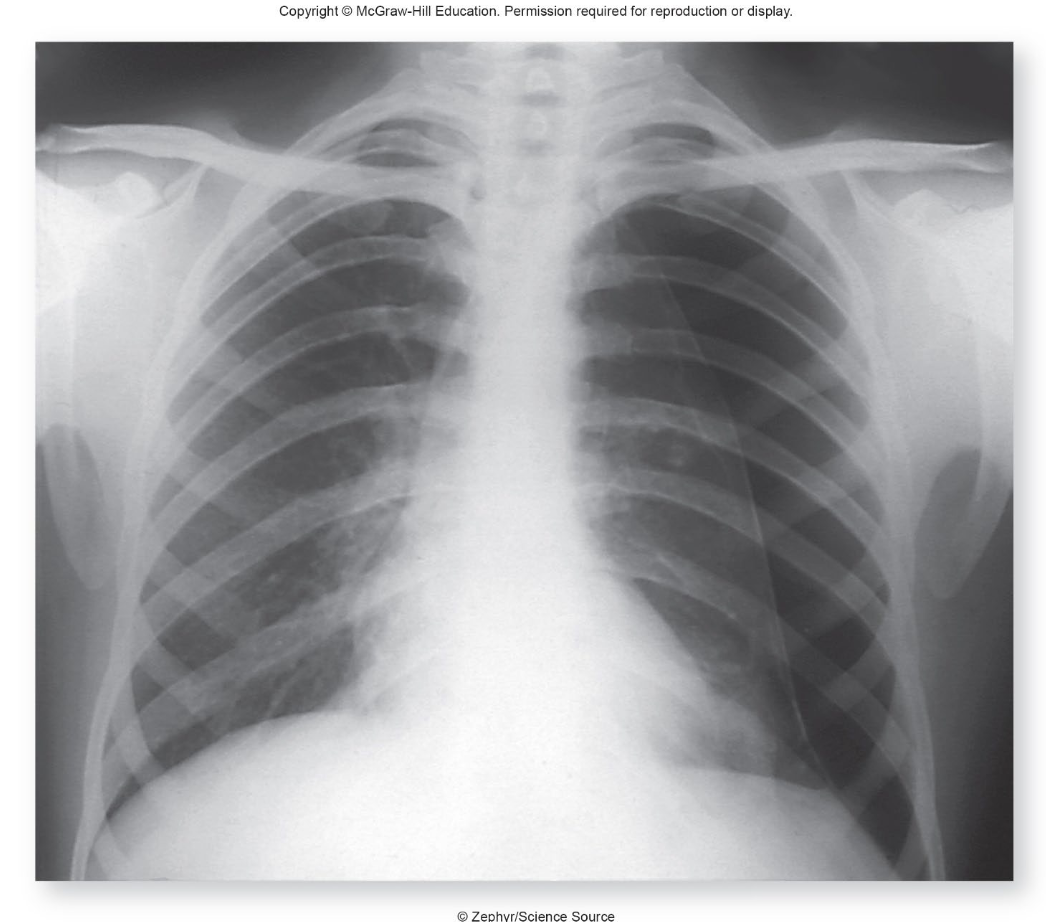

what is pneumothorax?

a condition where air enters the pleural space, leading to lung collapse due to pressure imbalance. It can be caused by trauma, disease, or spontaneously. when looking at imaging the collapsed side with be darker due to more air in the lungs